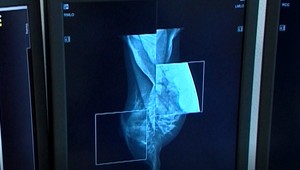

Pomoc chorým ženám v UNB: Lekári dokážu šetrne vyhľadať v prsníku aj nehmatateľný nádor Zdravie a diagnózy